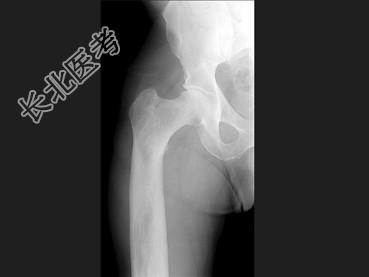

单项选择题男,67岁, 右侧股骨痛,结合图像, 最可能的诊断是 ( )

A、骨纤维结构不良

B、维生素D缺乏病

C、成骨不全

D、软骨发育不全

E、畸形性骨炎